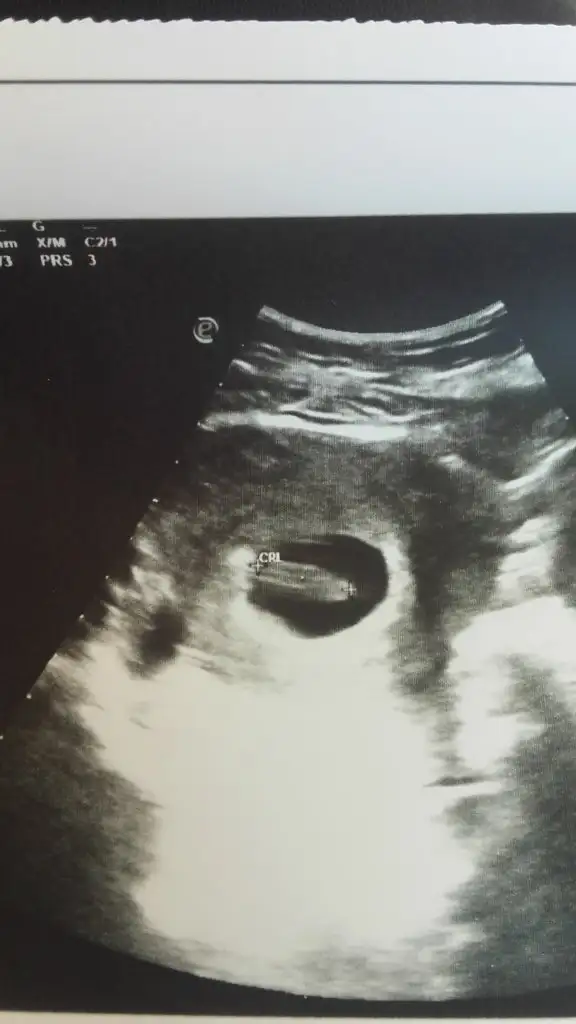

solda mi sanki?Eki Görüntüle 2542717 Eki Görüntüle 2542717 birde bana yorum yapın

5+5 göre erkek 7+5 olmuyor kese konumu artık bebek yer değiştiriyor o haftalarda dediğim gibi kese tutmaya biliyor en iyi sonuç nub teorisi bakalım sizde kese tutacakmı 5+5 göre erkek tatlım